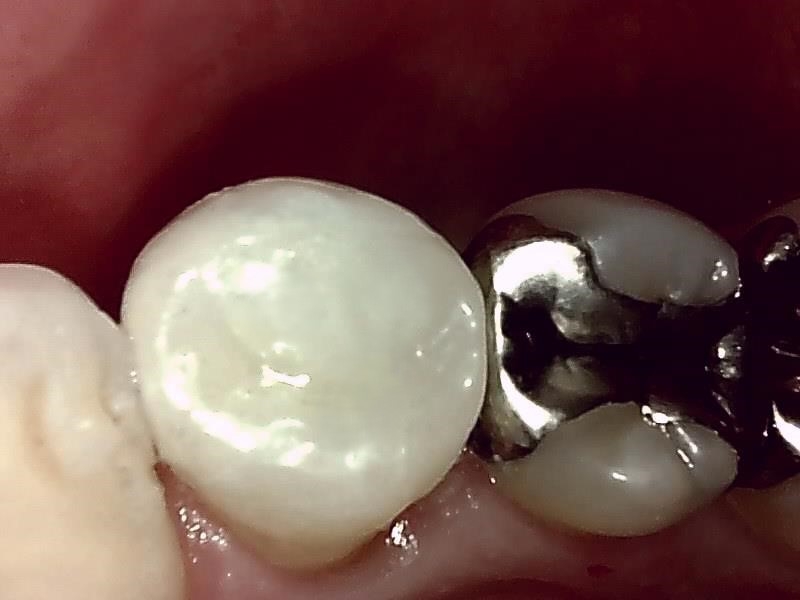

部位:左下8番骨性完全埋伏歯

切開 歯肉剝離

抜歯窩

歯肉を切開し、歯が見えるようにして、

周辺の骨を削らないように親知らずを分割し抜きやすくしていきます。

この抜歯法により術後の腫れ痛みが大幅に軽減されます。

傷口は最小限に、骨は極力削らずに行います。

骨が歯を覆っているケース以外は骨を削ることはありません。

親知らずのみにアプローチし歯を分割し最小限の傷口で取り出します。

縫合

抜歯後、経過良好です。